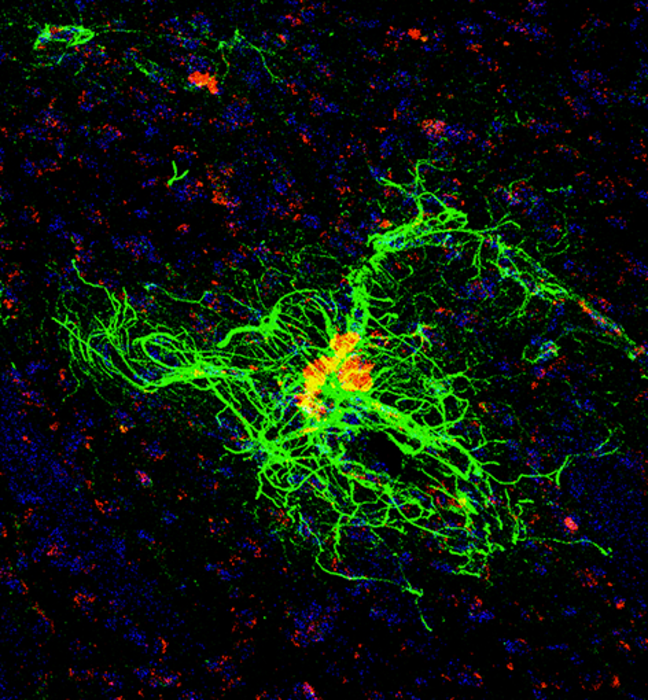

La “proteína gliofibrilar ácida”, más conocida por sus iniciales en inglés GFAP,refleja cambios en el cerebro por la enfermedad de Alzheimer/ UCI School of Medicine

La “proteína gliofibrilar ácida”, más conocida por sus iniciales en inglés GFAP,refleja cambios en el cerebro por la enfermedad de Alzheimer/ UCI School of Medicine“En el futuro podría utilizarse como biomarcador no invasivo de la activación precoz de células inmunitarias como los astrocitos en el sistema nervioso central, lo que puede ser valioso para el desarrollo de nuevos fármacos y el diagnóstico de enfermedades cognitivas”, añadió la científica.